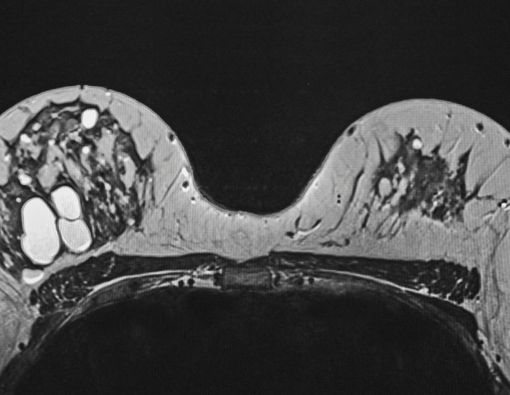

4. Mamografi pada Wanita Muda Lebih Sulit Ditafsirkan

Payudara wanita berusia sangat muda mengandung lebih banyak kelenjar dan ligamen. Hal tersebut membuat jaringan payudara tampak padat, sehingga dapat mengaburkan tanda-tanda kanker.

Oleh karena itu, pemeriksaan mamografi baru dianjurkan untuk dilakukan secara berkala oleh wanita yang berusia 40 tahun atau lebih.